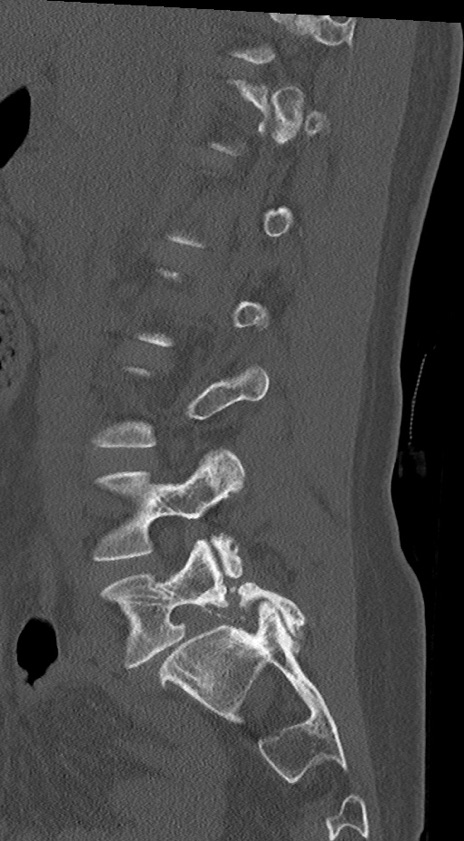

腰椎CT

冠状断像